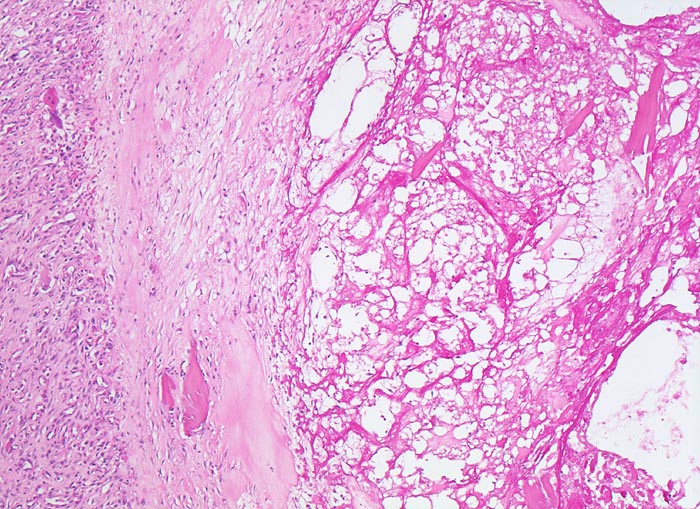

Coxarthrose: Geröllzyste

Randbereich einer Geröllzyste. Im Zentrum der Zyste nekrotischer Detritus mit avitalen Knochenfragmenten. Die Geröllzyste wird umgeben von einem Saum Narbengewebe und daran anschliessend gefässreichem Granulationsgewebe.

74-jährige leicht adipöse Patientin mit Anlaufschmerz, belastungsabhängigem Schmerz und zunehmender Versteifung im Hüftgelenk. Im Röntgenbild des Hüftgelenks zeigen sich eine Gelenkspaltverschmälerung, subchondrale Osteolysen, Usuren und randständige Osteophyten.